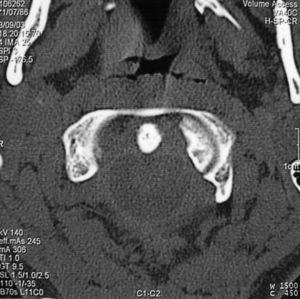

Paciente varón de 9 años con tortícolis asociada a fractura de clavícula por una caída en gimnasia. Tratado en su ciudad de origen mediante vendaje en 8 para la fractura de clavícula, y relajantes musculares y fisioterapia, fue remitido a nuestro centro a las 15 semanas por persistencia de la sintomatología (fig. 1). Las radiografías eran poco demostrativas, por lo que se practicaron estudios mediante TAC y RMN diagnosticándose de SRCAA tipo I3, con una divergencia C1-C2 de 42° (fig. 2); se instauró tracción halo-gravedad progresiva hasta un peso de 7 kg, en que se detuvo por aparición de disartria (17 días de tracción), con una movilidad rotacional levemente disminuida, la TAC de control mostró una divergencia residual de 11°, por lo que para evitar la recidiva se efectuó un artrodesis posterior C1-C2 in situ con injerto de cresta ilíaca (fig. 3), manteniendo la tracción durante la intervención e inmovilizándose con halo-yeso 3 meses. Una vez retirada la tracción, la disartria remitió espontáneamente. Quince años después, el paciente presenta una movilidad cervical prácticamente normal, con una limitación de la rotación izquierda de 10°.

Figura 2. Imagen de la tomografía axial computarizada (TAC) del paciente n.O 1 que muestra el método de medición, con una divergencia atlanto-axial de 42°.

El diagnóstico radiológico es difícil, ya que la deformidad y el dolor impiden obtener buenas proyecciones, así en la radiografía anteroposterior simple se superpone la cabeza, y en la lateral se puede observar una falta de paralelismo entre el cráneo y la columna; la radiografía transoral de odontoides puede ser de gran valor, mostrando una asimetría entre el diente del axis y las masas laterales del atlas con posible pinzamiento de las facetas8. Se ha sugerido la utilización de la TAC dinámica, con rotación a izquierda y derecha de la cabeza, pero en situación de SRCAA la movilización es dolorosa, por lo que difícilmente se obtendrá la cooperación del paciente, pudiendo llevar a confusión en el diagnóstico13. En una tortícolis aguda no parece estar indicado el estudio con TAC14,15, pero en casos persistentes con sospecha de SRCAA es muy útil para confirmar el diagnóstico, ya que mostrará la divergencia rotacional C1-C2 que se puede cuantificar midiendo la angulación existente entre las líneas que unen las apófisis transversas del atlas y del axis (fig. 2)16. En la TAC tridimensional se puede apreciar la deformidad rotacional con el desplazamiento completo de las facetas articulares, la situación asimétrica de la odontoides en el arco anterior del atlas --que asimismo puede orientar sobre la integridad del ligamento transverso-- y el desplazamiento de la espinosa de C24. La RMN es un buen complemento, ya que puede informar de interposición de partes blandas7, así como de la posible lesión del ligamento transverso17, por lo que en caso de duda puede indicar la necesidad de estabilización quirúrgica. En nuestra serie, ante una sospecha de SRCAA, se utilizó la TAC simple como método diagnóstico (fig. 2 y 4A), completándose en el tercer caso con reconstrucción tridimensional (fig. 4B) en la cual fueron muy evidentes las alteraciones torsionales del complejo atlantoaxial.